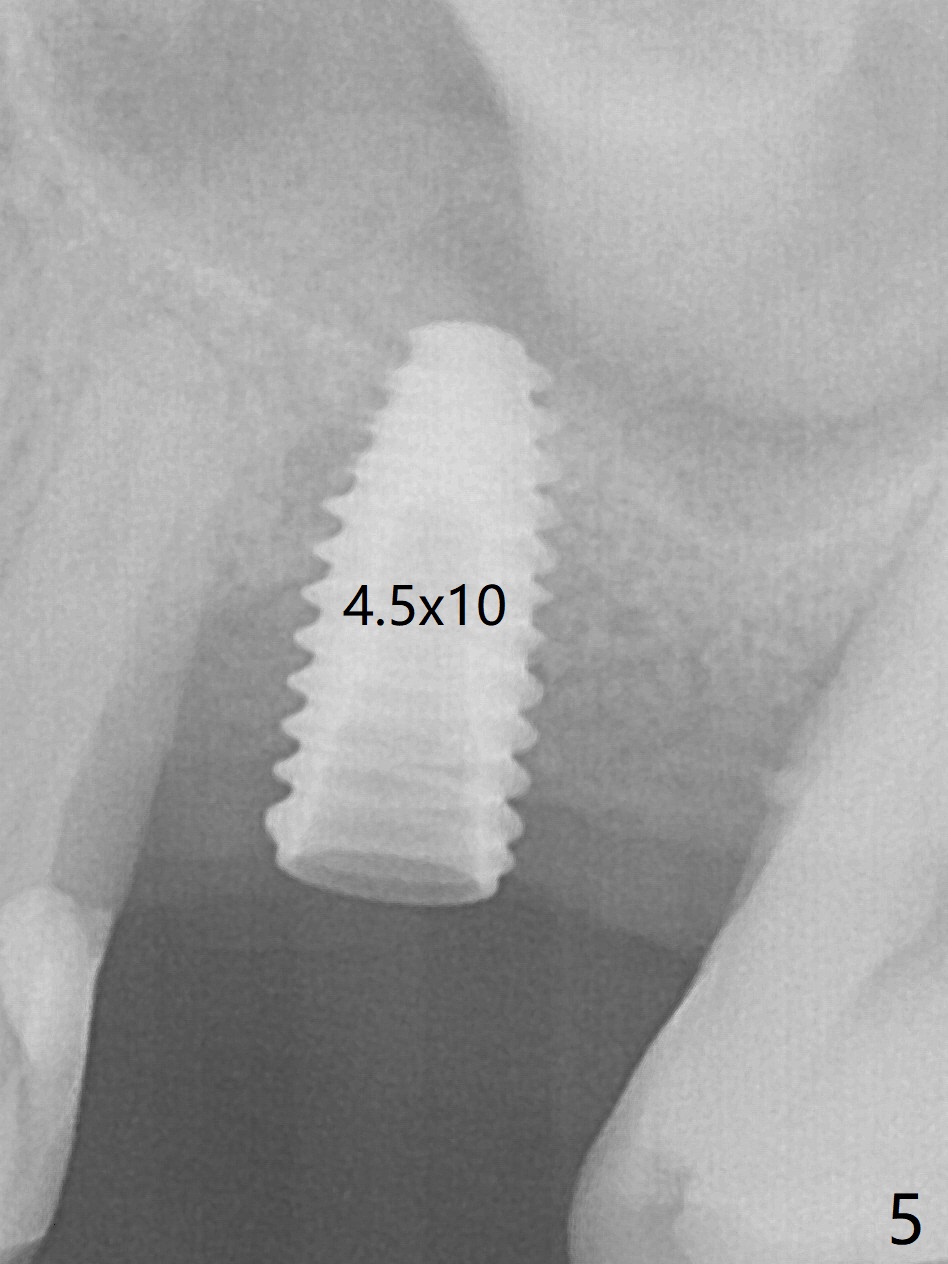

Trajectory of sinus lift without guide at #14 is off (Fig.1 (Magic Sinus Lifter (L) for 9 mm (gingival level)) and needs to be corrected (Fig.2 long line) by re-using 4.8 mm Magic Drill. Following placement of PRF membrane and Demineralized Cortical Allograft (.125-.850 mm) for sinus lift (Fig.3 black dashed line), a 4x10 mm dummy implant is placed with off trajectory. The latter will be fixed by using Lindmann bur to remove the bone distal (Fig.4). The result is less satisfactory with placement of 4.5x10 mm dummy implant (Fig.5). It appears necessary to initiate a new osteotomy (Fig.6 long black line). In fact the result is appealing (Fig.7). The final implant (5x7.3 mm) seems to be placed ideally shown by PA (Fig.8) and BW (Fig.9). Immediately postop CT demonstrates distal defect (Fig.10 *;3-D) and supracrestal placement palatal (Fig.11 P; coronal section). More allograft is then placed in these 2 areas. In all, it is difficult to establish a correct osteotomy without guide. The patient return for uncover 3.5 months postop, although there is a small hole in the middle of the incision (Fig.12). The crown/abutment becomes loose less than 1 month post cementation when the patient chews something tough. It is more related to the unfavorable implant/crown ratio. It is loose again 2 months later. Screw driver is buried inside the abutment with plumber tape. When it is loose for the 3rd time 13 months post cementation, the existing screw driver with a created slot (for retention) is buried without plumber tape after retorque at 35 Ncm (Fig.13). A tissue-level implant should have been used.